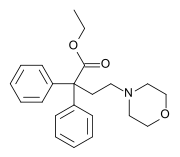

The first fully synthetic opioid was meperidine (later demerol), found serendipitously by German chemist Otto Eisleb (or Eislib) at IG Farben in 1932.[228] Meperidine was the first opiate to have a structure unrelated to morphine, but with opiate-like properties.[199] Its analgesic effects were discovered by Otto Schaumann in 1939.[228] Gustav Ehrhart and Max Bockmühl, also at IG Farben, built on the work of Eisleb and Schaumann. They developed "Hoechst 10820" (later methadone) around 1937.[230] In 1959 the Belgian physician Paul Janssen developed fentanyl, a synthetic drug with 30 to 50 times the potency of heroin.[211][231] Nearly 150 synthetic opioids are now known.[228]